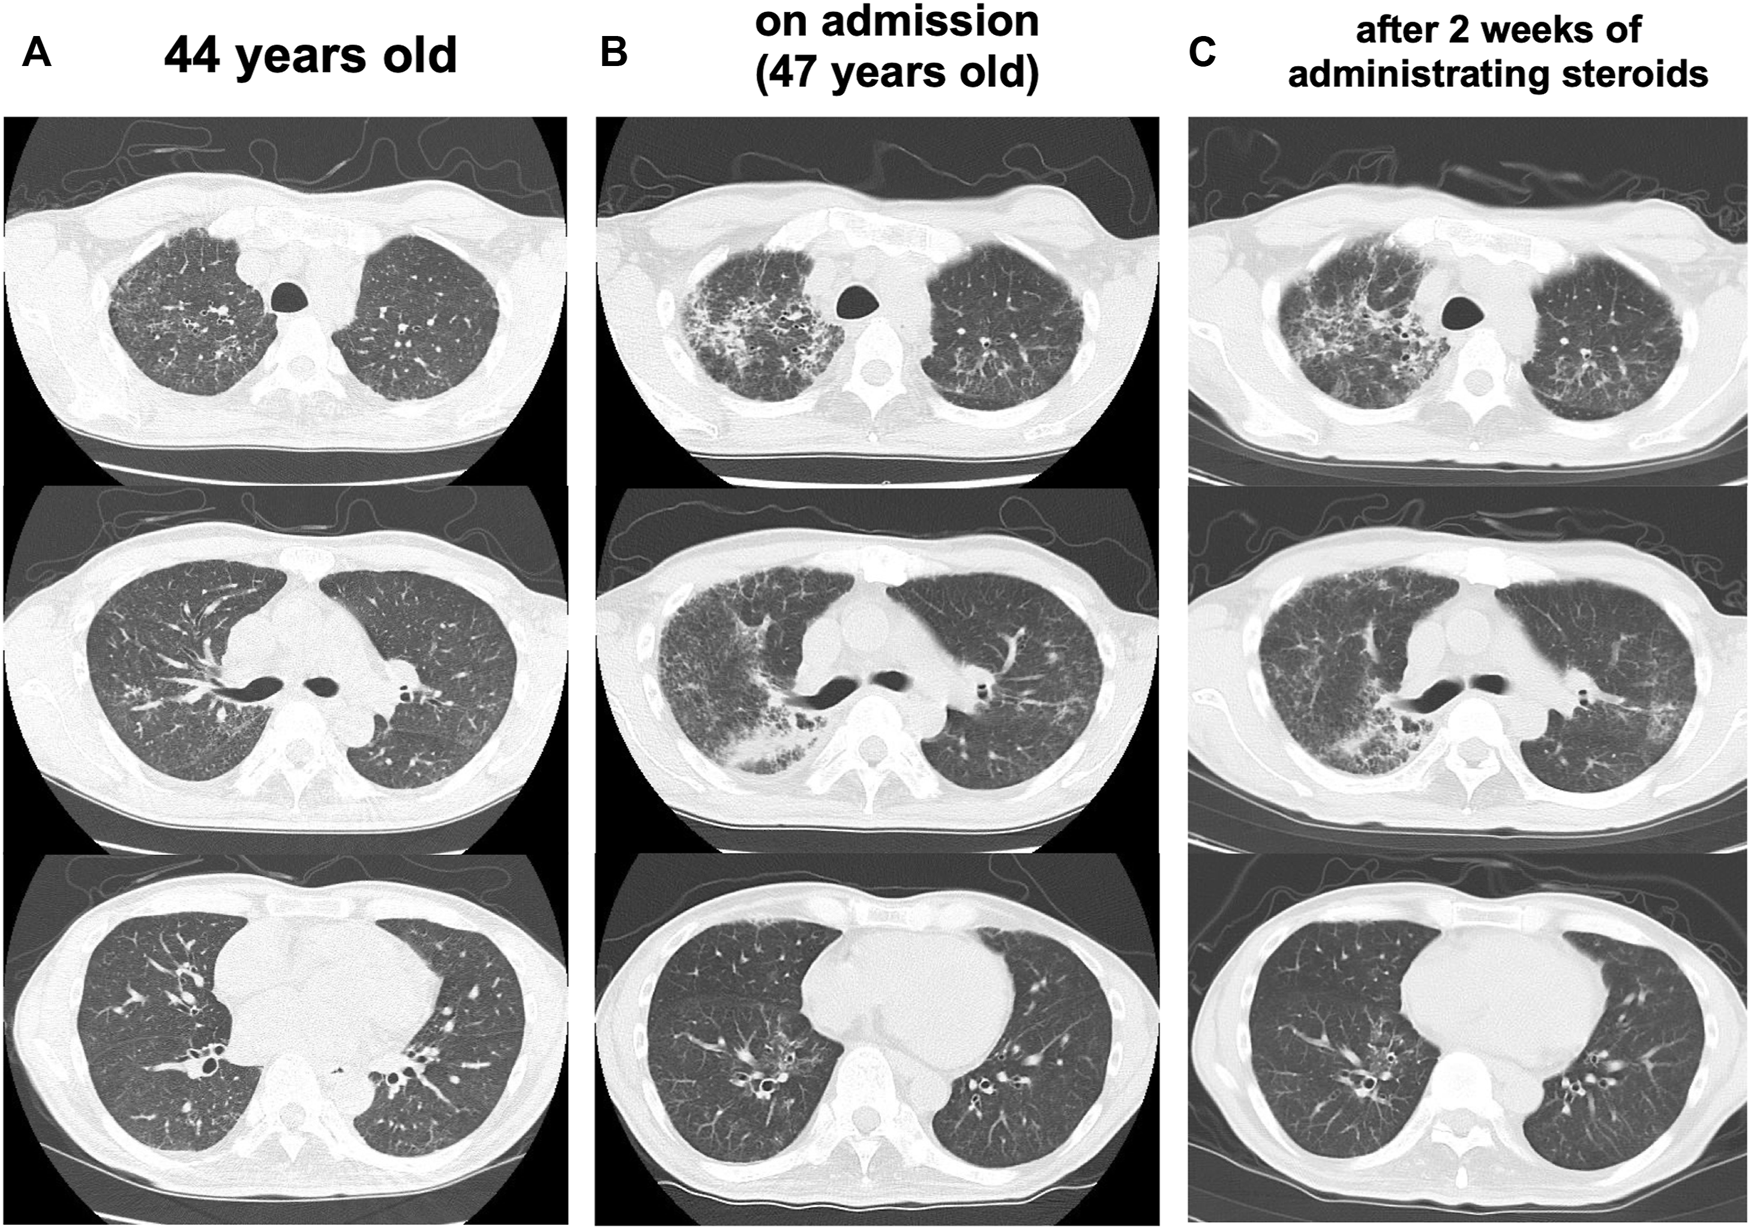

At the age of 47 years, his shortness of breath and interstitial lung shadows on chest CT worsened compared to those at 44 years of age (Figures 3A,B) immediately after recovery from bacterial pneumonia. His oxygen saturation was 94% in ambient air. Bilateral fine crackles were detected predominantly in the right upper fields on chest auscultation. Pulmonary function tests showed a restrictive ventilatory impairment (vital capacity [VC], 1.56 L; VC % predicted, 45.7%) and a decline in diffusing capacity (diffusing capacity for carbon monoxide % predicted [DLCO % predicted], 42.6%). The ratio of residual volume to total lung capacity was elevated (38.1%), indicating the presence of respiratory muscle weakness. Serum levels of Krebs Von den Lungen-6 (KL-6), surfactant protein A (SP-A), and surfactant protein D (SP-D) were elevated to 1,085 U/mL, 98.3 ng/ml, 505.6 ng/ml, respectively. Bronchoalveolar lavage (BAL) from the right upper lobe (B3b) revealed an increased proportion of neutrophils and eosinophils (macrophages, 82.0%; lymphocytes, 7.0%; neutrophils, 6.7%; eosinophils, 4.3%; CD4/CD8 ratio, 0.66) in the BAL fluid. Echocardiography results were within the normal limits. Based on these findings, an exacerbation of interstitial pneumonia was considered, and 40 mg/day of prednisolone was administered. 2 weeks later, his shortness of breath, interstitial shadows on the chest CT scan (Figure 3C), and markers of interstitial pneumonia improved. Serum levels of SP-A and SP-D decreased (62.9 ng/ml and 321.4 ng/ml, respectively), although serum KL-6 unchanged. Pulmonary function tests showed improvements in %VC and %DLCO (49.5 and 54.5%, respectively). However, shortly thereafter, he abruptly developed severe hepatic encephalopathy. Although he temporarily recovered after treatment with amino acid preparation and lactulose, there was no more effective treatment since he was already in a phase of hepatorenal syndrome. He finally developed severe hypoxemia due to worsening of bilateral pneumonia and pulmonary edema, which led to death within a few days. Subsequently, an autopsy was performed.

FIGURE 3

Progress of lung CT scans (A) At 44 years old (B) On admission (47 years old), the interstitial lung shadows worsened (C) 2 weeks after administrating corticosteroids, interstitial shadows were improved.